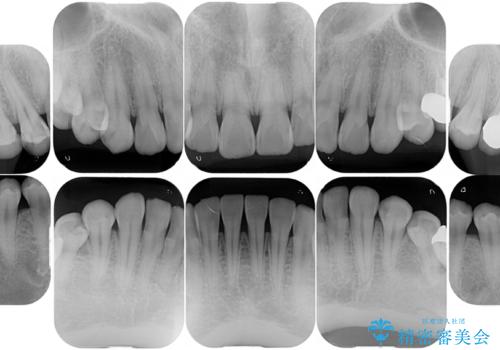

白い被せ物で一見綺麗に見えますが、適合が悪い詰め物や、セラミックが欠けているところが複数認められました。虫歯になってしまっているところもあり、全体的に治療しました。

右下の一番奥の歯は、元々かなり深いところまで削られていたため、歯周外科処置を行った上で補綴処置を行いました。